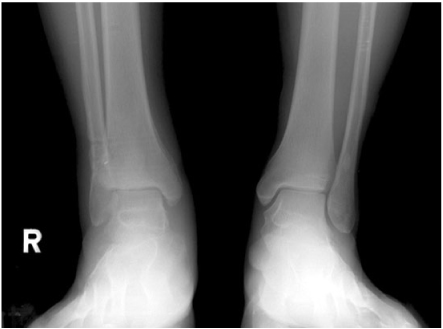

Fig. 7

Intra-operative ankle X-ray (AP and lateral views).

Fig. 7 Intra-operative ankle X-ray (AP and lateral views).